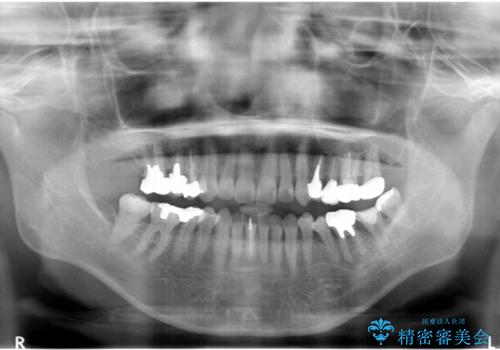

※術前にレントゲン・CTを撮影し、抜去する歯と親知らずの根の長さ・幅径・形態を確認し、移植の可否を判断してから手術を行っております。

左下の奥歯(左下7)は破折しており保存不可能な状態でした。

ご希望により、隣の親知らず(左下8)を移植しました。